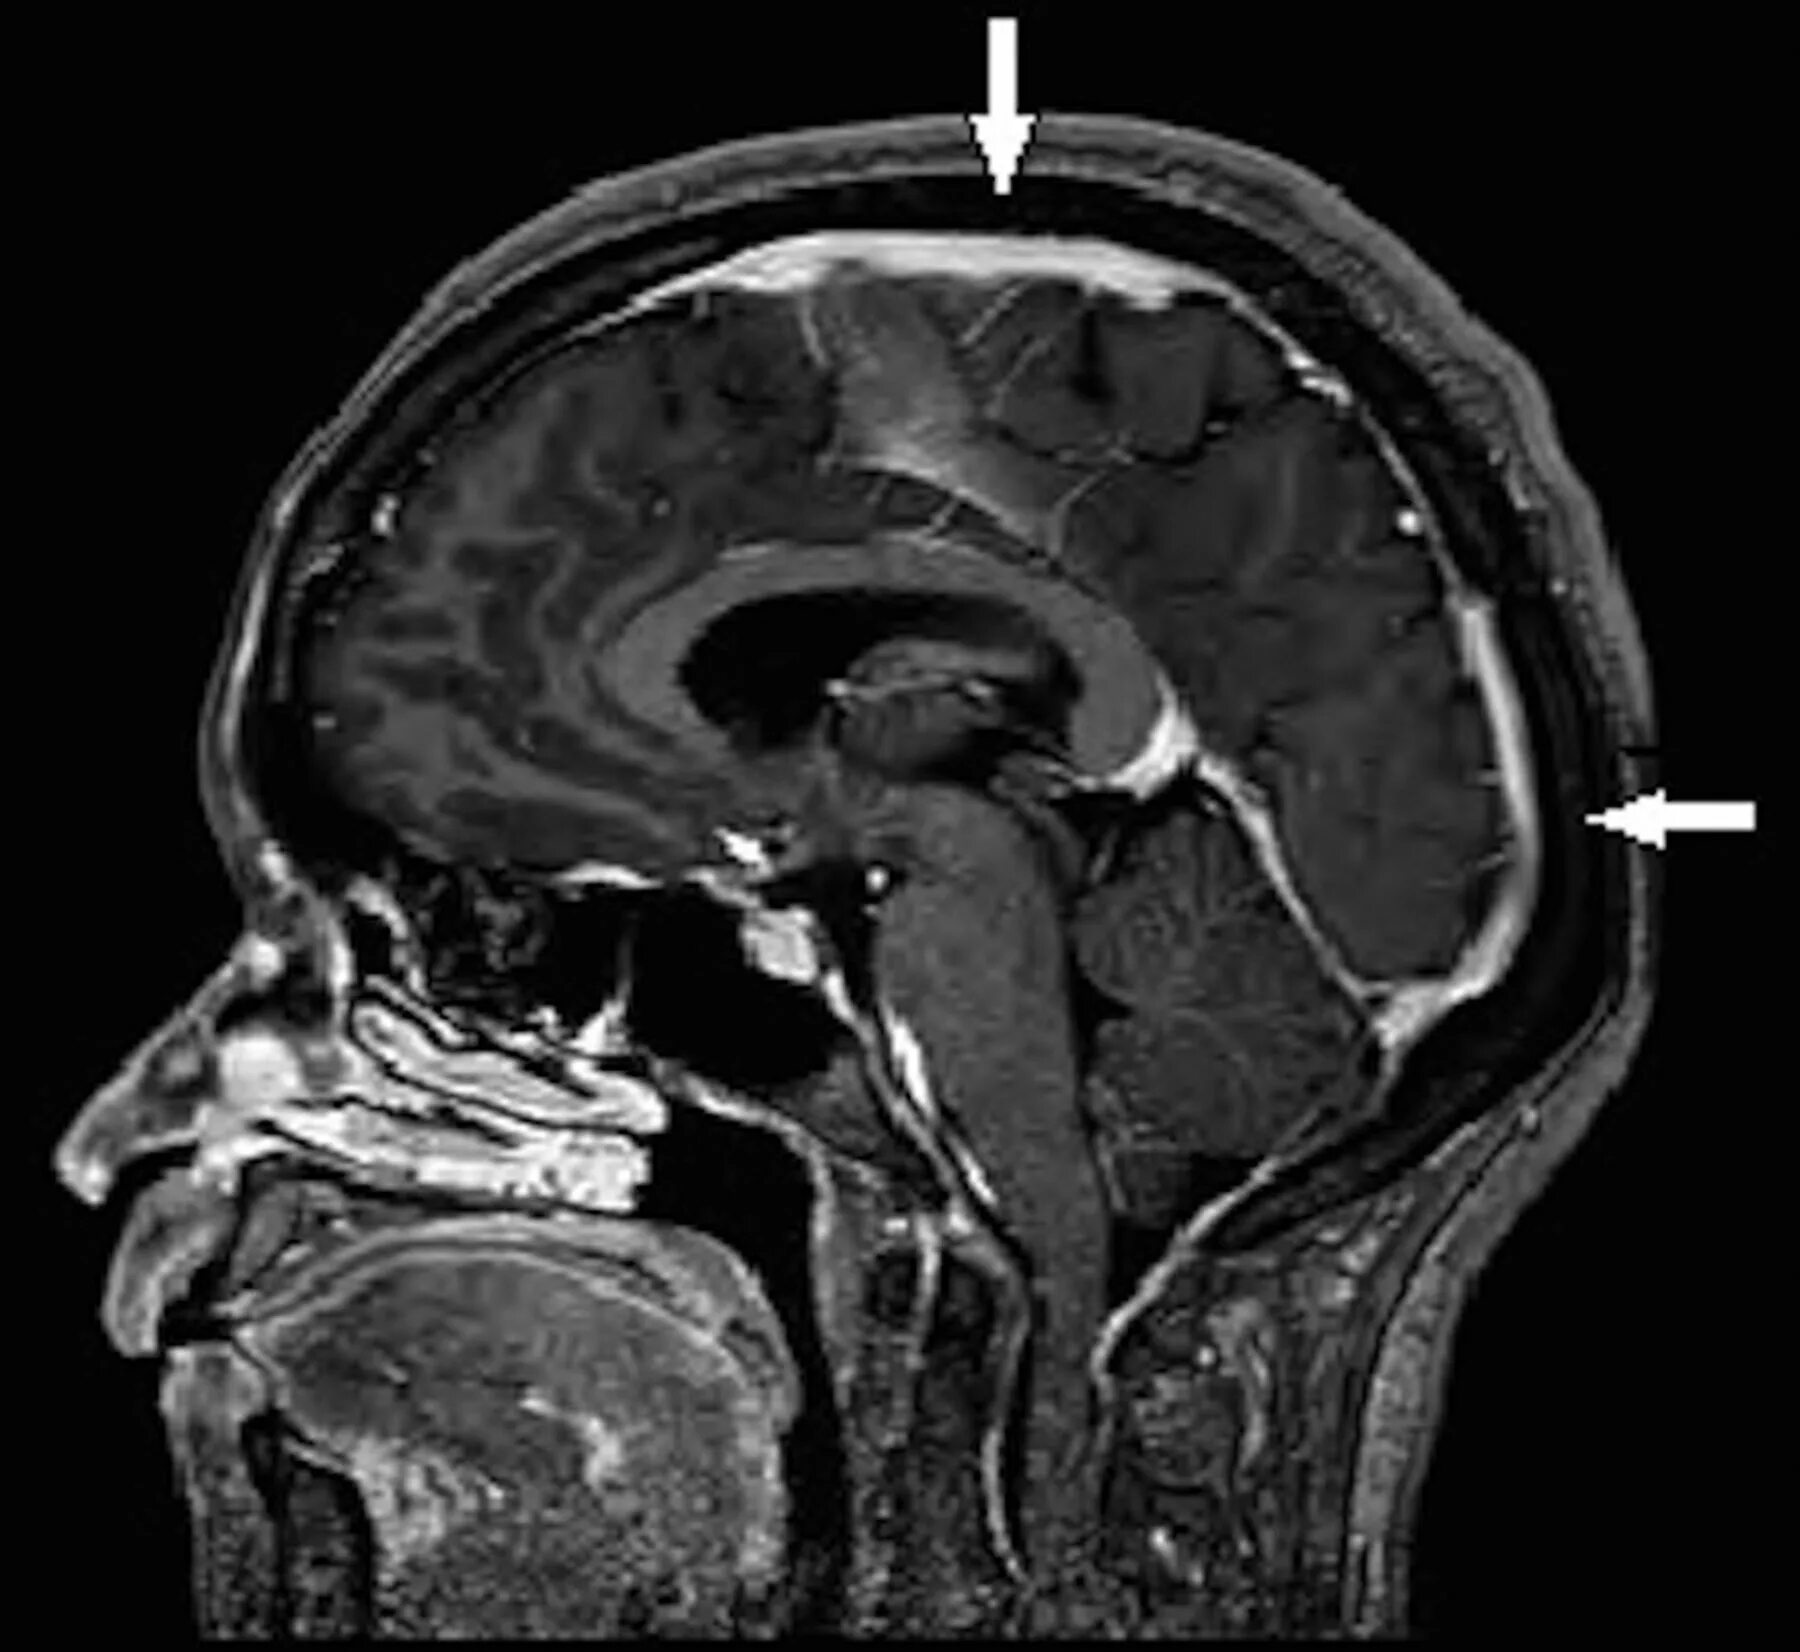

Расширенный субарахноидального конвекситального пространстваМрт головного мозга расширение субарахноидального пространства. расширение субарахноидальное конвекситальное пространство. расширение субарахноидального пространства у детей на мрт. субарахноидальное конвекситальное пространство расширено на кт.Расширение субарахноидальное конвекситальное пространство. мрт головного мозга расширение субарахноидального пространства. расширение наружных ликворных пространств головного мозга на мрт. расширение ликворных пространств головного мозга мрт.Расширенный субарахноидального конвекситального пространстваРасширенный субарахноидального конвекситального пространстваПодпаутинное субарахноидальное пространство. расширение субарахноидального пространства мозжечка. переднее субарахноидальное пространство спинного мозга. синдром арнольда-киари 1 типа.Расширенный субарахноидального конвекситального пространстваЦистерны подпаутинного пространства головного мозга. циркуляция ликвора анатомия схема. твердая мозговая оболочка головного мозга схема. субарахноидальное пространство топография.Расширенный субарахноидального конвекситального пространстваСубарахноидальное пространство головного мозга норма. подпаутинное субарахноидальное пространство. цистерны мозжечка анатомия. расширение субарахноидального конвекситального пространства норма.Субарахноидальное пространство мрт. конвекситальное субарахноидальное пространство. цистерны подпаутинного пространства головного мозга. субдуральное и субарахноидальное пространства.Расширение субарахноидального пространства кт. субарахноидальные пространства сужены.Расширенный субарахноидального конвекситального пространстваКонвекситальное субарахноидальное кровоизлияние кт. конвекситальные субарахноидальные пространства. локальное расширение субарахноидального пространства. локальное субарахноидальное кровоизлияние.Расширенный субарахноидального конвекситального пространстваРасширенный субарахноидального конвекситального пространстваРасширенный субарахноидального конвекситального пространстваРасширенный субарахноидального конвекситального пространстваМрт головного мозга расширение субарахноидального пространства. локальное расширение субарахноидального пространства. расширение субарахноидального пространства задней черепной ямки. субарахноидального конвекситального пространства.Расширенный субарахноидального конвекситального пространстваРасширение субарахноидального конвекситального пространства норма. ликворная киста лобной доли на кт.Расширенный субарахноидального конвекситального пространстваРасширенный субарахноидального конвекситального пространстваАрахноидальные пространства мозжечка. мрт головного мозга расширение субарахноидального пространства. расширение субарахноидальное конвекситальное пространство. расширение субарахноидальных пространств в лобно - теменных отделах..Расширенный субарахноидального конвекситального пространстваРасширение субарахноидальное конвекситальное пространство. мрт головного мозга расширение субарахноидального пространства. расширение конвекситальных субарахноидальных пространств симптомы. расширение субарахноидального пространства кт.Подпаутинное субарахноидальное пространство. субарахноидальное пространство головного мозга норма. расширение конвекситальных субарахноидальных пространств симптомы. субдуральное и субарахноидальное пространства.Расширение субарахноидального пространства на мрт. субарахноидальное конвекситальное пространство расширено на кт. расширение субарахноидальных пространств на кт. субарахноидальное пространство мрт.Расширенный субарахноидального конвекситального пространстваМрт головного мозга расширение субарахноидального пространства. гипоплазия червя мозжечка кт. локальное расширение субарахноидального пространства мрт. арахноидальная киста лобной доли.Субарахноидальное пространство головного мозга. расширение субарахноидального пространства. переднее субарахноидальное пространство. переднее и заднее субарахноидальное пространство.Расширенный субарахноидального конвекситального пространстваРасширенный субарахноидального конвекситального пространстваРасширенный субарахноидального конвекситального пространстваРасширенный субарахноидального конвекситального пространстваРасширенный субарахноидального конвекситального пространстваДиапедезное кровоизлияние в субарахноидальном пространстве. субарахноидальная гематома. расширение субарахноидального конвекситального пространства.Субарахноидальное пространство мрт. конвекситальные субарахноидальные пространства кт.Расширение субарахноидального пространства кт. субарахноидальное пространство кт головного мозга. расширение субарахноидального пространства на мрт. расширение ликворных пространств на кт.Субарахноидальное пространство мрт. субарахноидальное пространство головного мозга. цистерны субарахноидального пространства. субарахноидальное пространство мозжечка.Мозг анатомия ликвор. цистерна латеральной ямки большого мозга. цистерны подпаутинного пространства головного мозга. оболочки головного мозга синусы и цистерны.Мрт головного мозга расширение субарахноидального пространства. головной мозг сагиттальный срез мрт. расширение субарахноидального пространства на мрт. субарахноидальное пространство норма мрт.Расширенный субарахноидального конвекситального пространстваКонвекситальные субарахноидальные пространства расширены. локальное расширение субарахноидального пространства. расширение субарахноидального пространства головного мозга.Конвекситальные субарахноидальные пространства. расширение субарахноидального пространства кт. расширение субарахноидального пространства головного мозга. расширение субарахноидального пространства на мрт.Расширенный субарахноидального конвекситального пространстваРасширенный субарахноидального конвекситального пространстваРасширенный субарахноидального конвекситального пространстваСубарахноидальные пространства умеренно расширены. расширение субарахноидальных конвекситальных пространств. степени расширения субарахноидального пространства у взрослых. субарахноидальное пространство расширено.Расширенный субарахноидального конвекситального пространстваРасширенный субарахноидального конвекситального пространстваРасширенный субарахноидального конвекситального пространстваМрт головного мозга заключение. заключение мрт картина. расширение субарахноидального пространства головного мозга. субарахноидального конвекситального пространства.Расширение субарахноидального пространства кт. арахноидит головного мозга на кт. расширение ликворных пространств на кт. расширение субарахноидального конвекситального пространства норма.Расширенный субарахноидального конвекситального пространстваРасширение субарахноидального пространства кт. субарахноидальное конвекситальное пространство расширено на кт. субарахноидальное пространство мозга. расширение субарахноидального пространства на мрт.Цистерны подпаутинного пространства. подпаутинное субарахноидальное пространство. паутинная оболочка мозга анатомия. расширение подпаутинного пространства головного мозга.Цистерны подпаутинного пространства головного мозга. конвекситальное субарахноидальное пространство. субарахноидальное пространство спинного мозга. подпаутинное субарахноидальное пространство.Субарахноидальное конвекситальное пространство лобные. конвекситальные субарахноидальные пространства кт. конвекситальные ликворные пространства на кт. расширение субарахноидального пространства у лобных долей.Расширенный субарахноидального конвекситального пространстваРасширенный субарахноидального конвекситального пространстваРасширенный субарахноидального конвекситального пространстваСубарахноидальные кисты. расширение субарахноидального пространства кт. конвекситальные субарахноидальные пространства расширены. расширение субарахноидального пространства головного мозга.Расширенный субарахноидального конвекситального пространстваАрахноидальная ликворная киста мрт. расширение субарахноидального пространства на мрт. арахноидальная киста гипофиза мрт. конвекситальная арахноидальная ликворная киста мрт.Расширенный субарахноидального конвекситального пространстваРасширенный субарахноидального конвекситального пространстваРасширенный субарахноидального конвекситального пространстваРасширенный субарахноидального конвекситального пространстваРасширение ликворных пространств мрт. локальное расширение субарахноидального пространства мрт. расширение наружных ликворных пространств головного мозга на мрт. расширение субарахноидального пространства у детей на мрт.Мрт головного мозга расширение субарахноидального пространства. вентрикуломегалия боковых желудочков. посттравматическая гидроцефалия кт. расширение субарахноидальных пространств головного мозга у взрослых.Расширение субарахноидальное конвекситальное пространство. конвекситальные борозды расширены что это. субарахноидальные пространства мрт норма. расширение конвекситальных пространств.Расширенный субарахноидального конвекситального пространстваКт при субарахноидальном кровоизлиянии. кт головного мозга при субарахноидальном кровоизлиянии. субарахноидальное нетравматическое кровоизлияние лечение. мрт субарахноидального кровоизлияния.